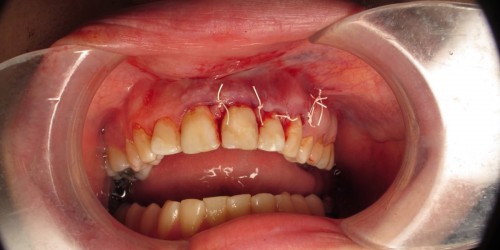

An apicoectomy was performed on tooth #11 approximately 5 months ago and I am still experiencing the exact pain existing before the procedure. I feel ill and very low energy. My endodontist checked my xray post-op and said it has healed nicely and looks fine. My ears ring and I have pain and pressure treatment site. Any suggestions?